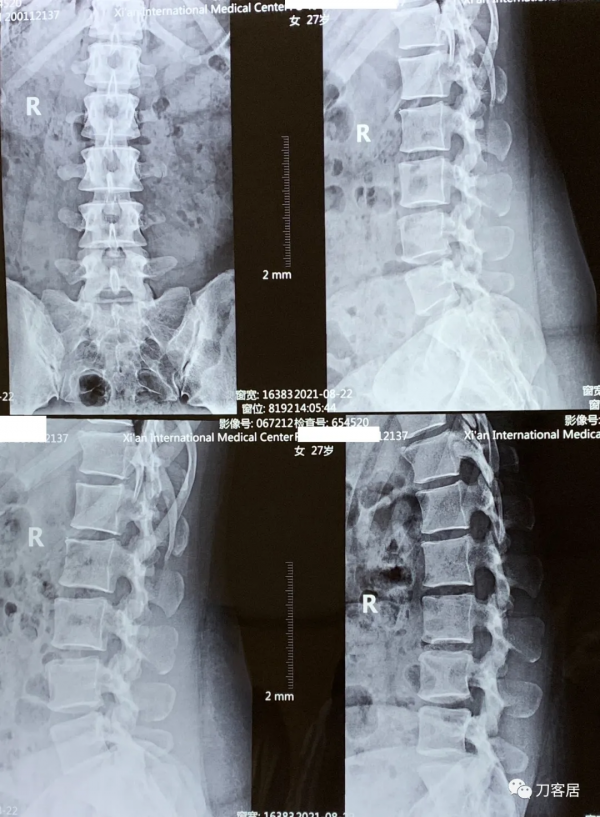

圖1. 20210822術前腰椎正側位及過伸過屈位X線片,我個人覺得,這個腰椎的穩定性尚可,但腰4-5椎間隙前屈後伸時變化還是有的。